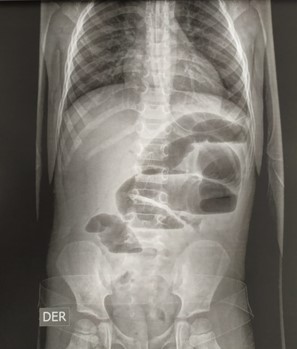

Una radiografía simple de abdomen estando de pie mostró mala distribución del aire, distención de las de asas intestinales, ausencia de aire en el espacio pélvico y niveles hidroaereos (Figura 1). El ultrasonido abdominal no estaba disponible en el hospital en ese momento.

Figura 1. Radiografía simple de abdomen en bipedestación con mala distribución del aire, distensión asas, ausencia de aire en el espacio pélvico, niveles de líquidos y gases.